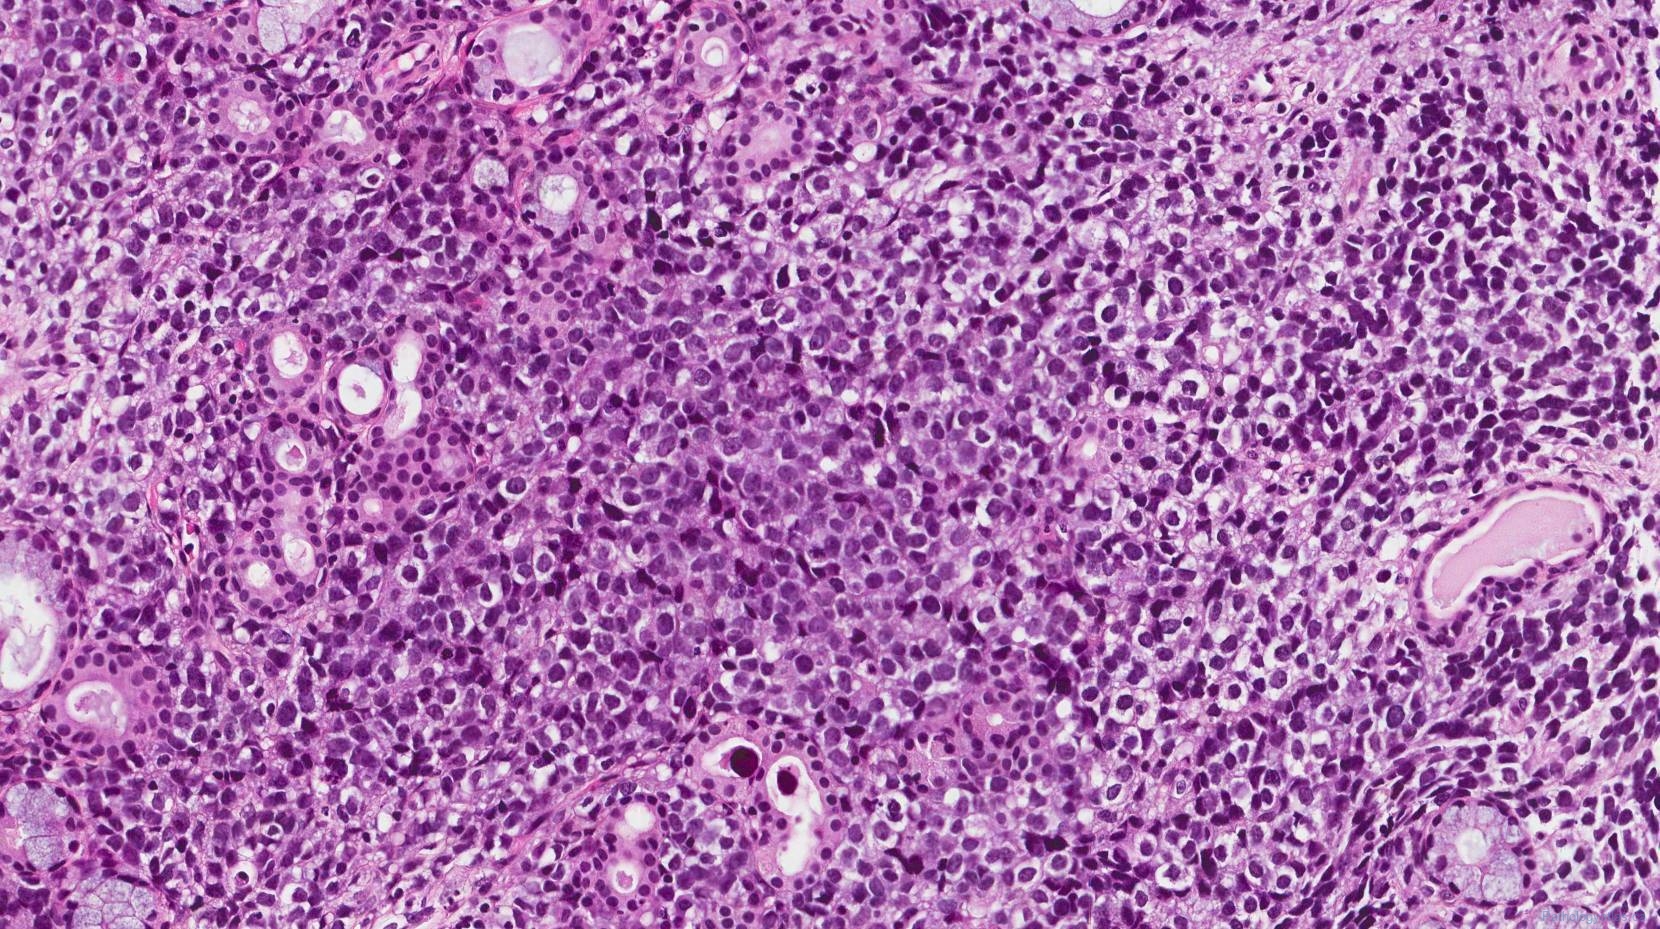

Soft Tissues: Alveolar Rhabdomyosarcoma

Alveolar Rhabdomyosarcoma | Basicmedical Key

alveolar rhabdomyosarcoma composed preservation tumor cellular cells peripheral round

Alveolar Rhabdomyosarcoma | Basicmedical Key

rhabdomyosarcoma alveolar nests tissue infiltrated epithelium fibrous extensively overlies postnasal respiratory sheets seen space type

Alveolar Rhabdomyosarcoma | MyPathologyReport.ca